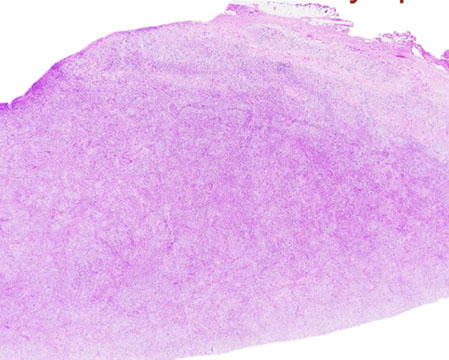

Cutaneous lymphoid hyperplasia in a 72-year-old man who presented with several purple-brown plaques on his cheeks and temples. A, The nodular infiltrate extends through the dermis with sparring of the overlying epidermis. B, It is characterized by scattered follicles with well-defined, reactive-appearing germinal centers, some of which have surrounding mantle zones. Many CD20-positive B cells are in the reactive follicles (C), and more numerous CD3-positive small T cells are present in the interfollicular areas (D). B-cell clonality studies (not shown) were negative for a clonal IGH or IGK gene rearrangement. [19]